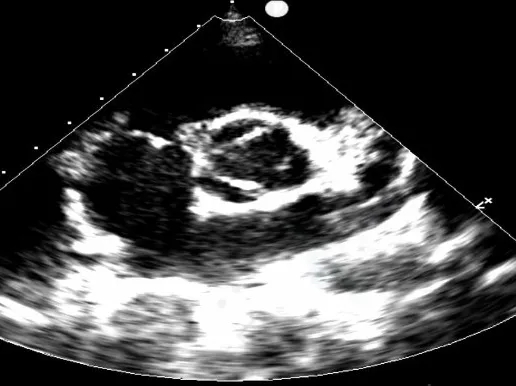

门诊心脏彩超提示:

超声多切面示:室间隔膜周部可见连续中断,局部不规则向右室膨出,呈“囊袋状”,断端回声增强,测缺口大小:左室面6.5mm、右室面2.5mm,隔瓣下残缘5mm,彩色血流示:室水平左向右分流,Vmax 473cm/s,Pgmax 89 mmHg。

各房室腔大小及大血管内径未见异常。各瓣膜厚度、弹性、开放幅度正常,彩色血流示:三尖瓣反流(少量),长度1.51cm、面积1.4cm2,容积1.0ml,Vmax 216cm/s,PGmax 16mmHg。据三尖瓣反流法估测肺动脉收缩压为28 mmHg;左室收缩功能正常,EF为74%。

术前超声与DSA复测

VSD(膜周部):室间隔膜部瘤,左室面6.5mm,右室面呈“瘤样”结构,瘤体深度7mm,出口2mm。